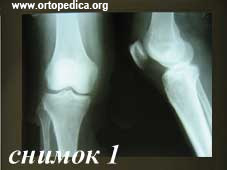

1. Рентгенограмма до операции